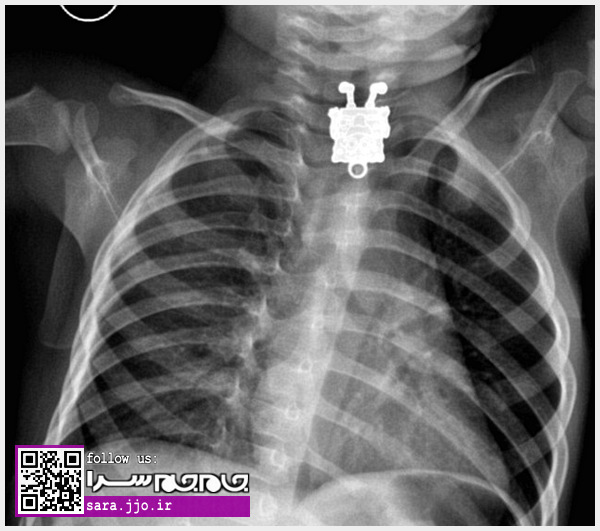

پزشکان در کشور عربستان سعودی از مشاهده تصویر یک عروسک که داخل مری کودک ۱۶ ماهه گیر کرده بود شوکه شدند. این کودک نوپا آویز گردنبند خواهر خود را بلعیده بود و دچار علائمی مانند تنگی نفس و مشکل در بلع شده بود.

بررسیها نشان میدهند، پزشکان در ابتدا پی نبرده بودند که چه مشکلی برای این کودک پیش آمده است و با انجام عکسبرداری اشعه ایکس موفق به یافتن ردپای این شی در مری او شدند.

اگرچه کودک نجات یافت اما نکتهٔ منحصر به فرد در این حادثه به دست آمدن یک تصویر کاملا واضح از گردن آویز نیز بود! چراکه حتی جزئیات طرح باب اسفنجی در گردنبند قابل مشاهده بود و کارشناسان این پدیده را در دنیای تصویر برداری با اشعه X شگفت انگیز ذکر کردهاند. (باشگاه خبرنگاران)